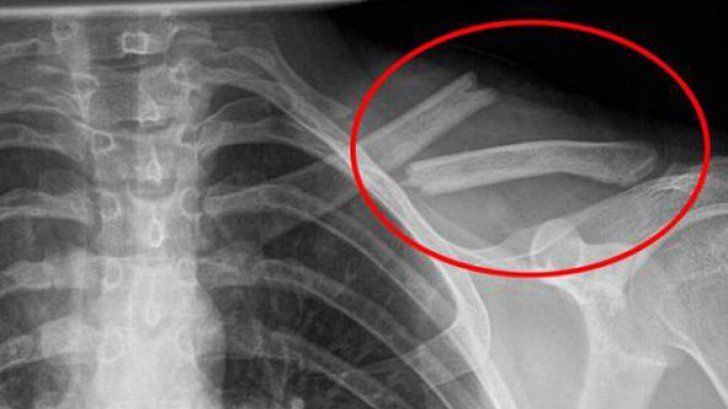

9 nov. 2017, 17:10ActualOtrava asta îţi distruge oasele, însă o bei în fiecare zi! Sigur nu ştiai asta!

3 aug. 2017, 18:42ActualOtrava asta îţi distruge oasele, însă o bei în fiecare zi! Sigur nu ştiai asta!

10 iun. 2017, 12:28ActualOtrava asta îţi distruge oasele, însă o bei în fiecare zi! Sigur nu ştiai asta!

17 dec. 2016, 12:32ActualOtrava asta îţi distruge oasele, însă o bei în fiecare zi! Sigur nu ştiai asta!